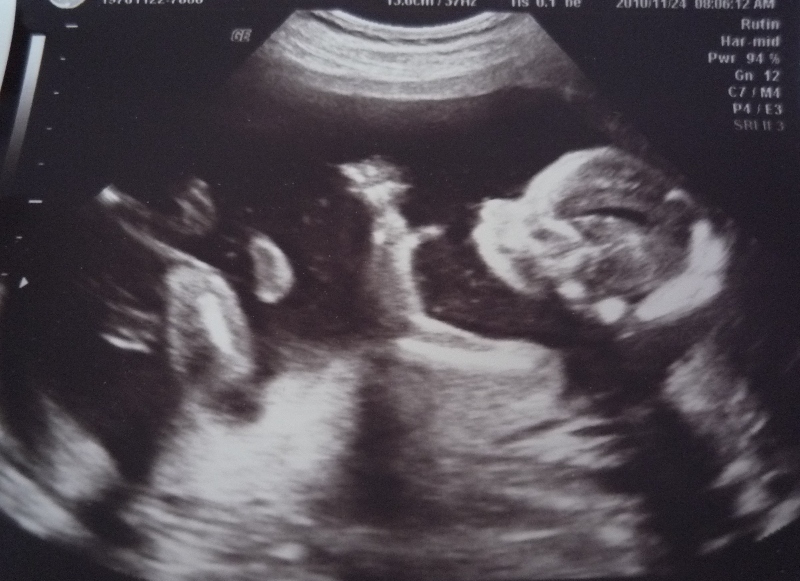

そして昨日、初めての超音波検査を受けてきました。

スウェーデンでは健康な妊婦であれば超音波検査は1回のみ。

5ヶ月目に入った私も、やっと超音波検査を受けることとなりました。

エコーを通して見えたお腹の赤ちゃんは

元気に手足を動かしていました。

胎動は既に毎日感じているものの、

妊婦であることを改めて実感した瞬間でした。

病院の助産師によるエコーは約30分ほど。

胎児に異常がないかを一通り確認し、頭の幅や足の長さを測定して

出産予定日が割り出されました。(4月下旬です)

特に心臓に関してはお医者さんがやって来てじっくりと診てくれました。

結果、問題なし。

エコーも検診もすべて無料ですが、エコー写真が欲しい場合は有料。

それでも50kr.のみ。3ショットもらえました。